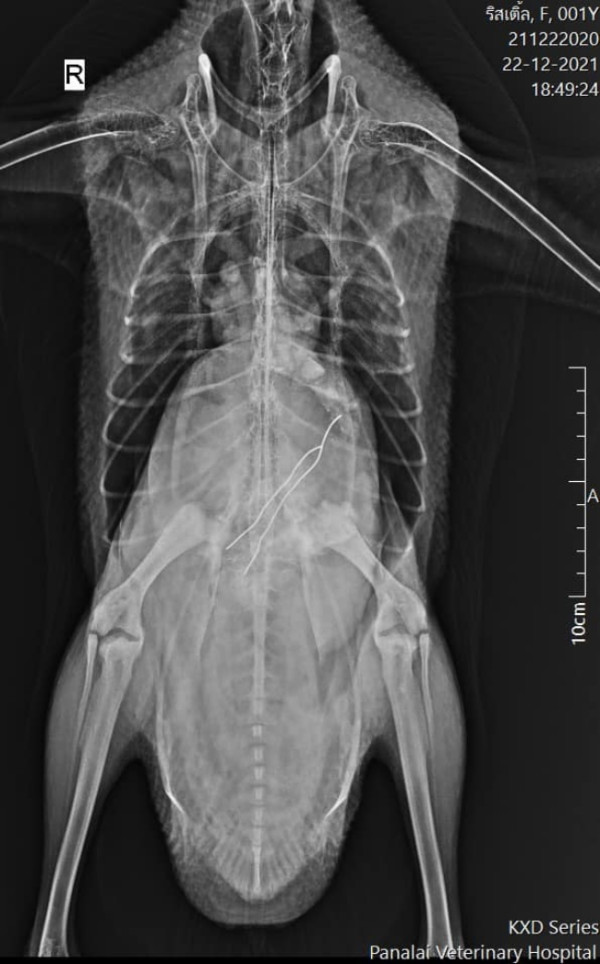

醫院的 X 光顯示,電線卡在小鵝的身體內,必須透過手術才能取出。在麻醉後,醫生為牠剃掉腹部的毛髮並進行手術。術後,小女鵝一臉無辜地攤平在手術床上,兩隻小腳直挺挺地擺著,鵝爸爸則關切地探頭查看,宛如在叮嚀:「下次別再把什麼東西都放進嘴巴裡!」